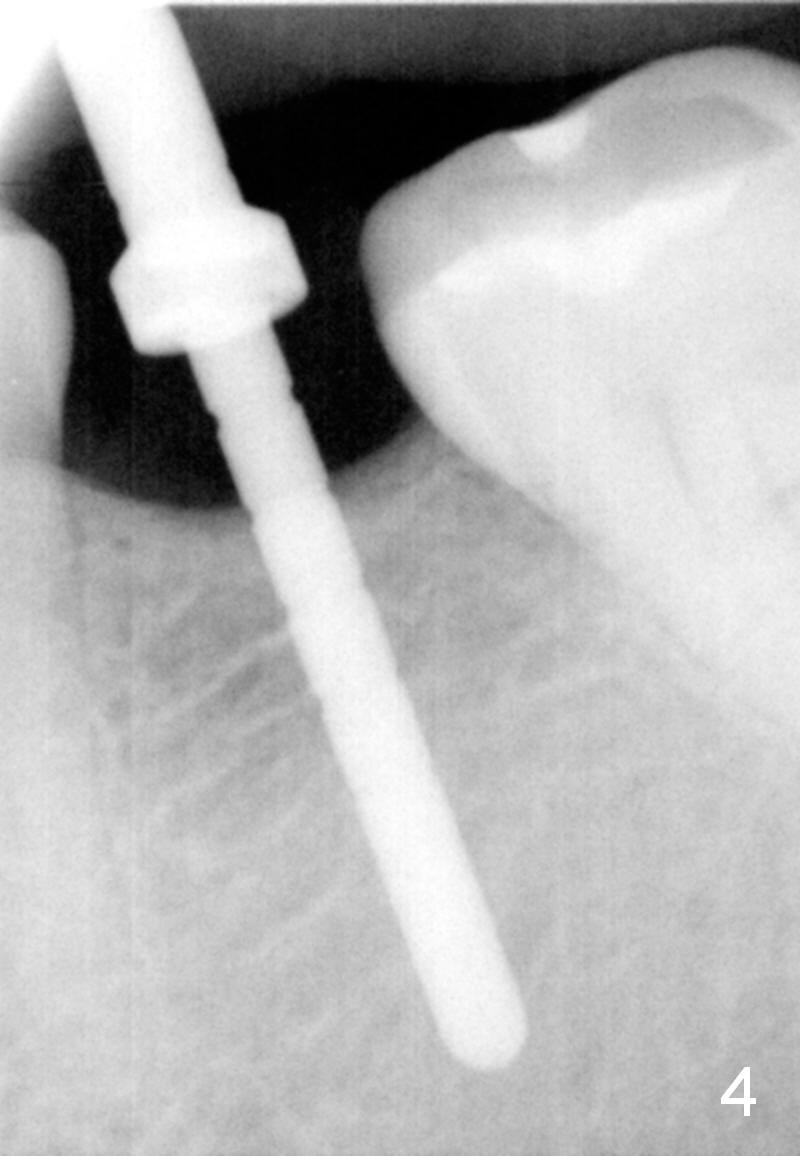

In fact, the buccolingual width of the ridge is sufficient to have a 4.5x11.5 mm implant placed (Fig.4,5, D3 bone, <35 Ncm). Proximal reduction is done before and after placement of a 5.5x4(3) mm abutment. Heavy abutment height adjustment is provided as well as the opposing prior to immediate provisional.